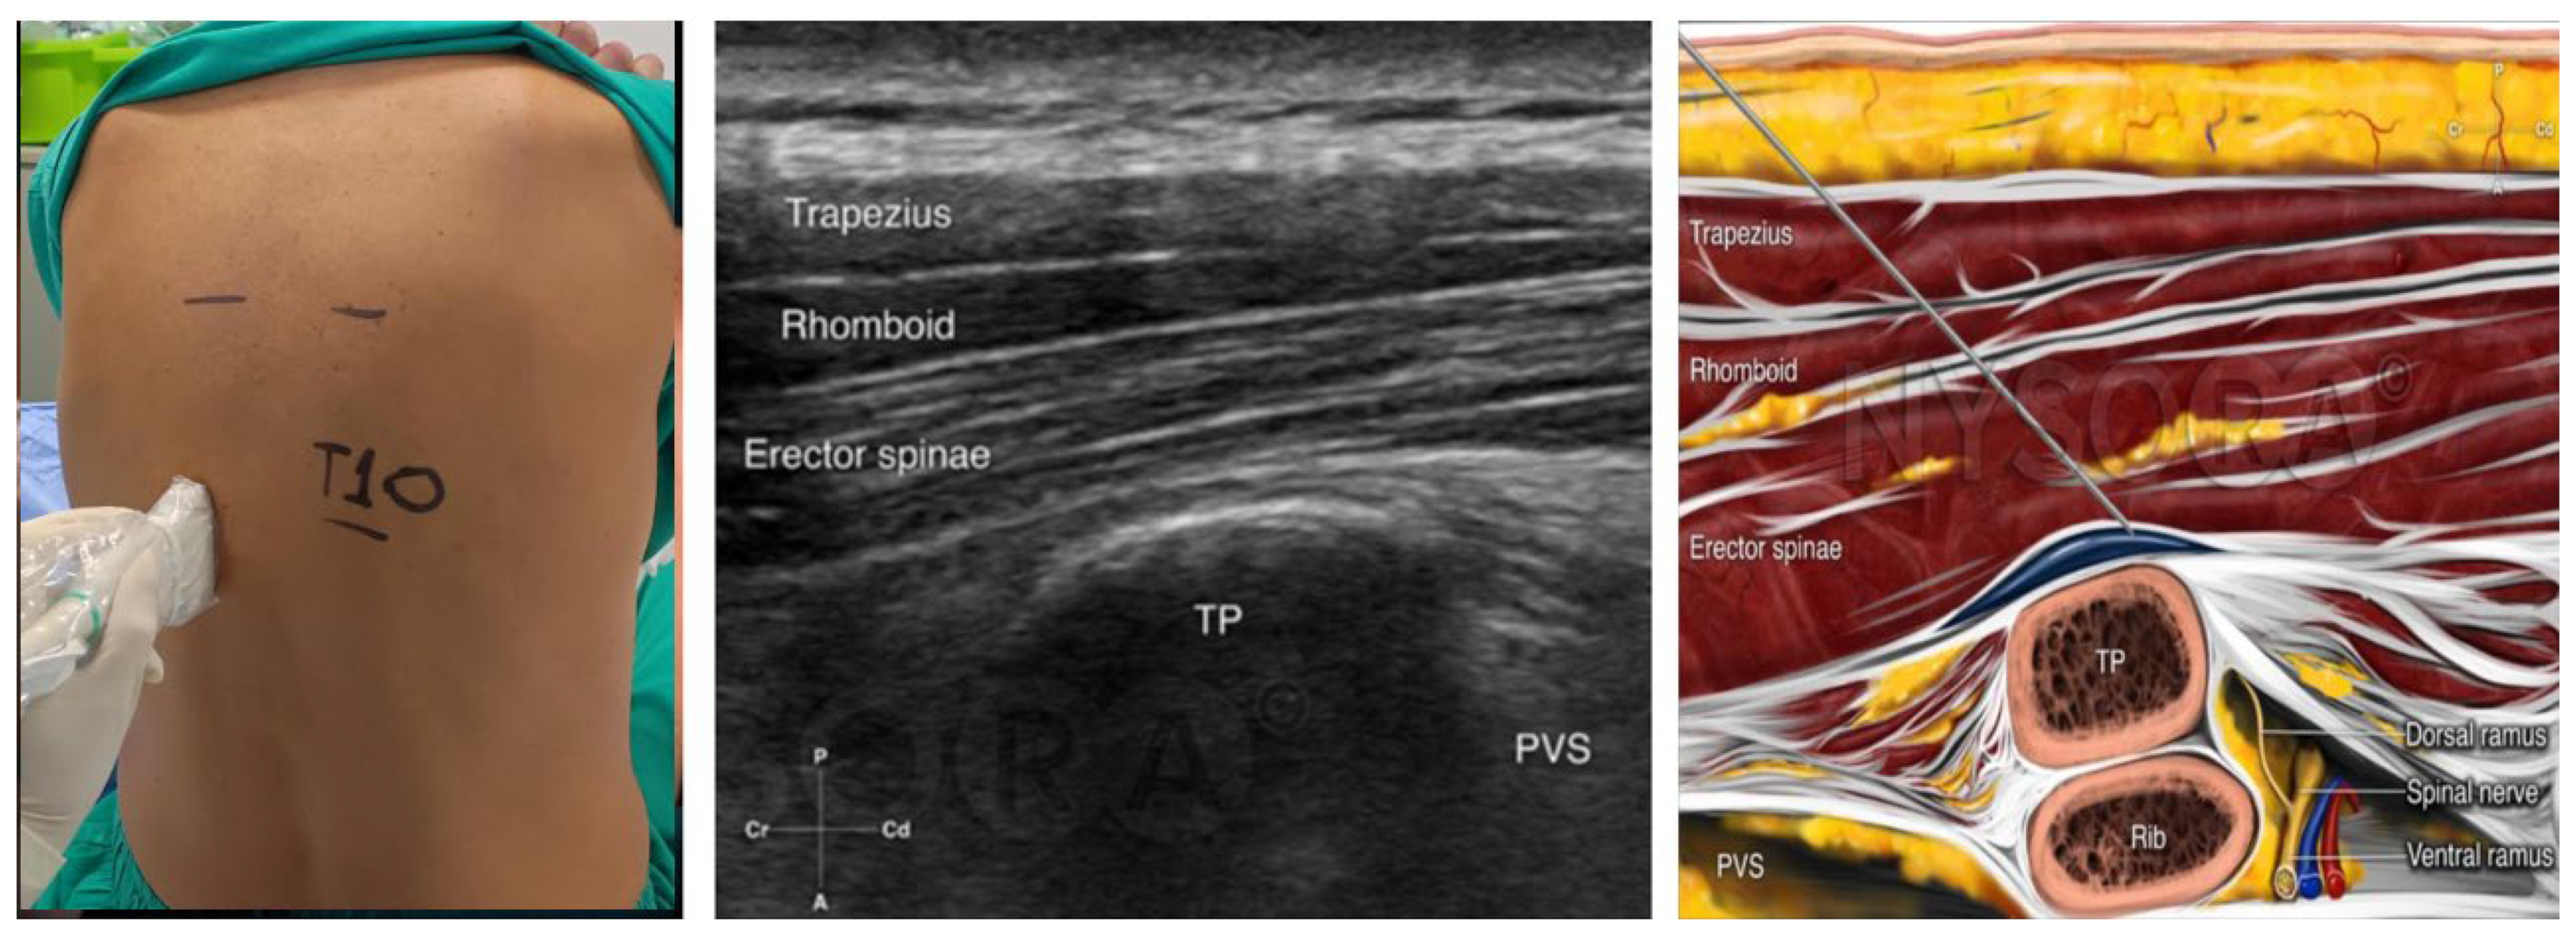

Bilateral erector spinae plane block (ESPB) was administered to all participants while in the seated position, 30 min before the initiation of general anesthesia. This procedure was performed under ultrasound guidance, utilizing a linear transducer (7–13 MHz) and an 80 mm, 22-gauge, short bevel needle. Initially the transducer was placed transversely on the spinous process of T10, and 3 cm laterally, the transverse process of T10 was identified. Subsequently, the transducer was repositioned sagittally, and the correct landmarks were identified. The needle was then inserted in a cephalad-to-caudad orientation, employing an in-plane technique. The needle was advanced, and 20 mL of the prepared solution was administered in the fascia between the transverse process and the erector spinae muscle, at each side. After completion of the block, a catheter for the continuous infusion of local anesthetic was inserted on each side (see Figure 1).

Figure 1.

Erector spinae plane block. The transducer is placed in transverse position on the preferred spinous process, and 3 cm laterally, the transverse process of the vertebra that is selected is identified. The transducer is turned sagittally, and the landmarks (trapezius muscle, rhomboid muscle, erector spinae muscle, and transverse process) are identified. The needle is inserted in a cephalad-to-caudad orientation and an in–plane technique is performed. The needle is advanced until its tip reaches the fascia between the transverse process and the erector spinae muscle and the local anesthetic is administered [8]. The figure was reprinted with permission from source: NYSORA.COM.